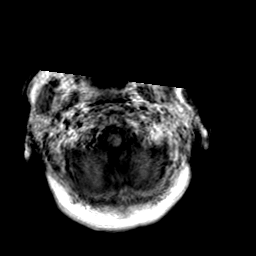

Creutzfeld-Jakob disease: gadolinium enchanced T1-Weighted MR -- Slice #1

[Home][Help][Clinical] Slice 1